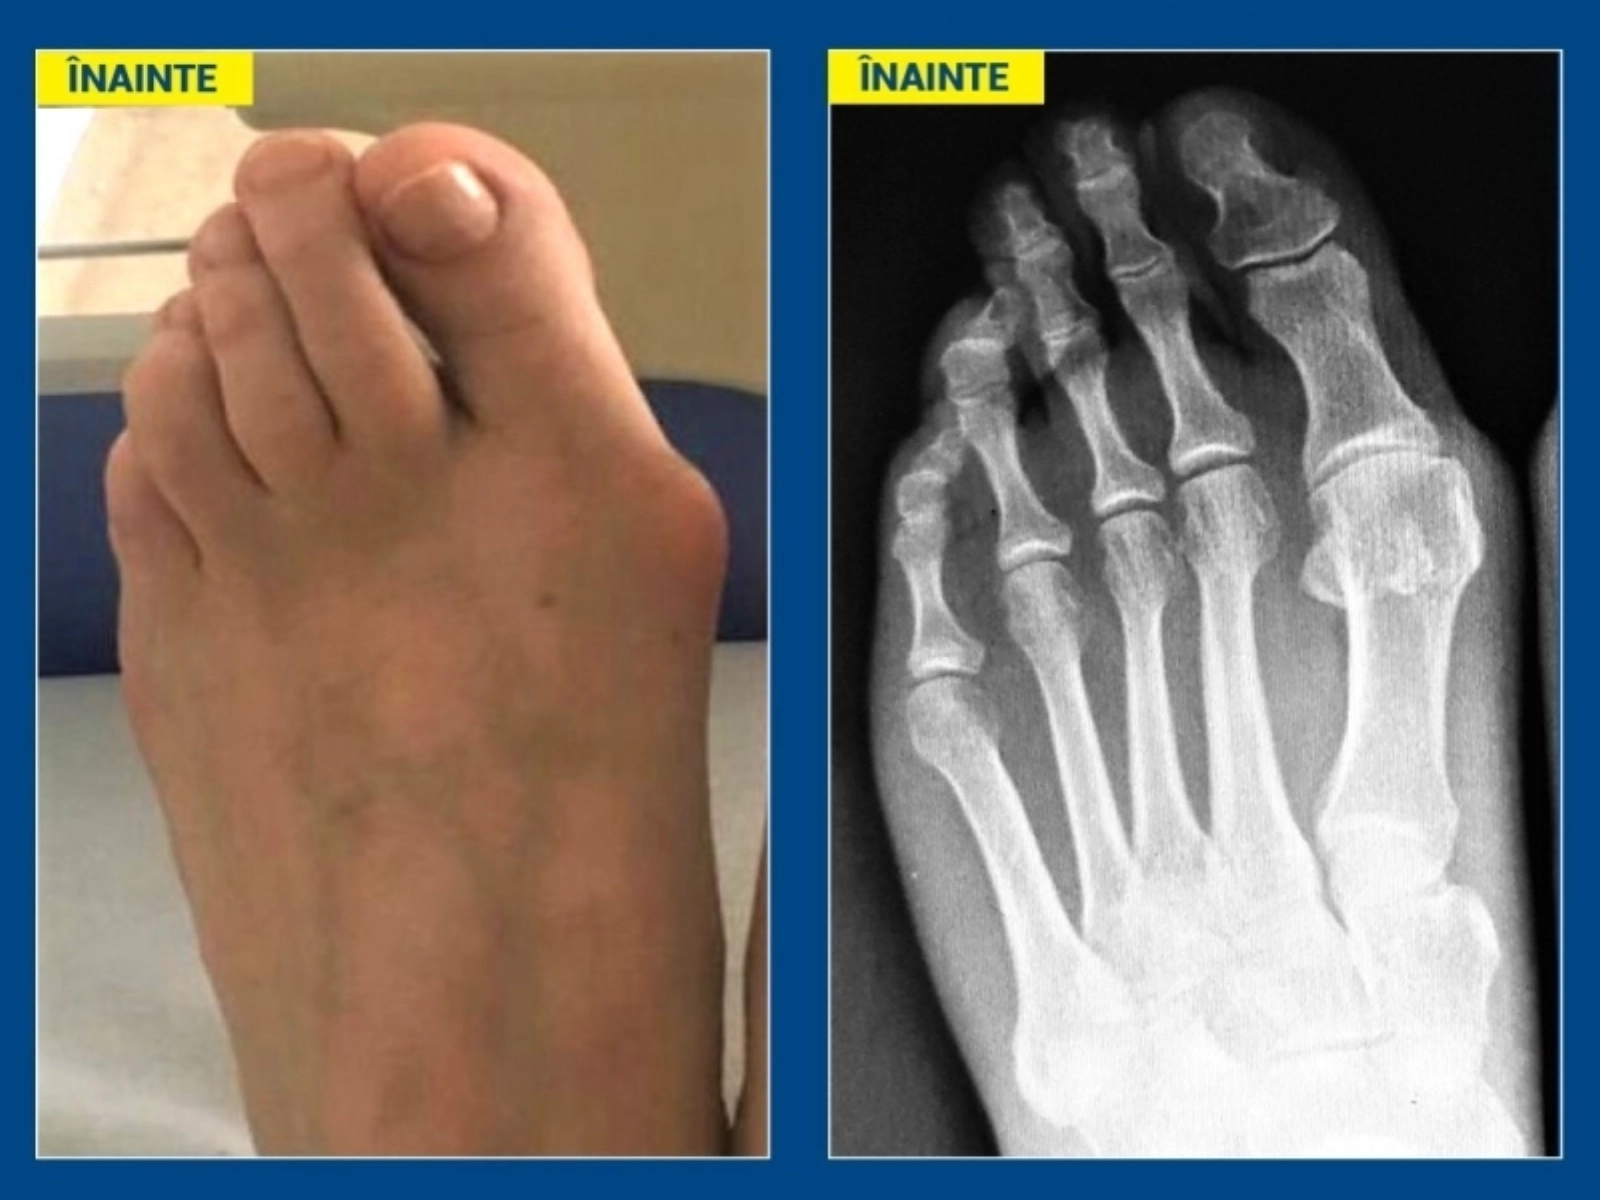

Monturile sau hallux valgus sunt deformări ale antepiciorului, apărute prin devierea osului de la baza halucelui (degetul mare) către interior, astfel încât capul acestui os proemină sub piele („montul”), în timp ce degetul mare este deviat către lateral, către degetele mici, pe care le împinge și, ulterior, le forțează să se „încalece”.

Intervenția de înlăturare a monturilor este una rapidă și nedureroasă, pacientul putând să revină la activitățile cotidiene chiar începând de a doua zi. Trebuie însă să poarte sandale ortopedice speciale încă din prima zi după operație, timp de minimum o lună de zile.

Riscul de recidivă a monturilor există, dar acesta este cu atât mai mic cu cât operația este făcută mai devreme, din timp (atunci când diformitatea nu este foarte avansată) și este efectuată corect (de către un medic cu experiență). Evitarea purtării pantofilor cu toc și vârf îngust duce, de asemenea, la scăderea riscului de recidivă.